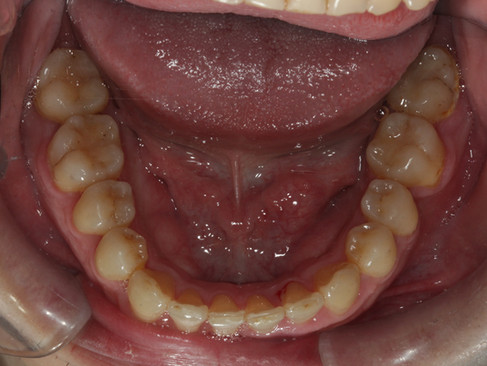

治療前:

右上第一小臼齒跟左下第一小臼齒都蛀掉了,附近有牙齒擁擠的情況,

左下有完整萌發出來的智齒!

我們決定將右上缺牙空間關閉,將左下智齒往前拉,取代被拔掉的缺牙,

病患便不需要植牙或做假牙了